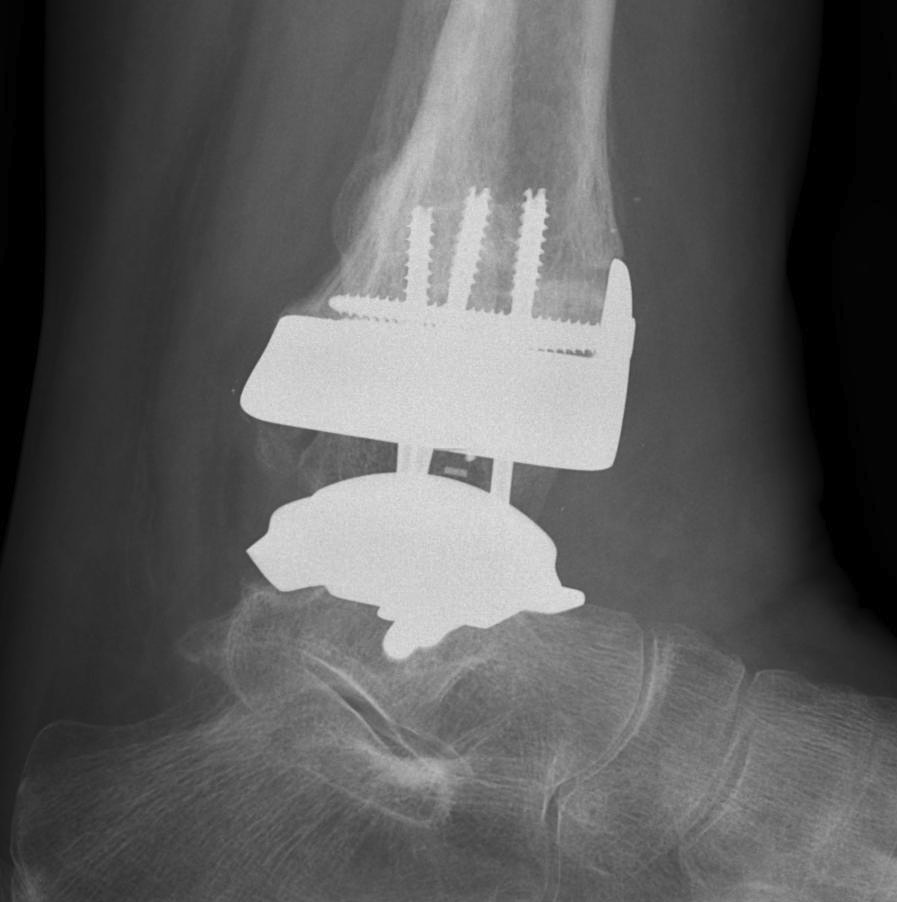

B. Lateral approach and fibular osteotomy

Zimmer Biomet Trabecular Metal PDF

Vumedi fibula osteotomy approach for total ankle arthroplasty